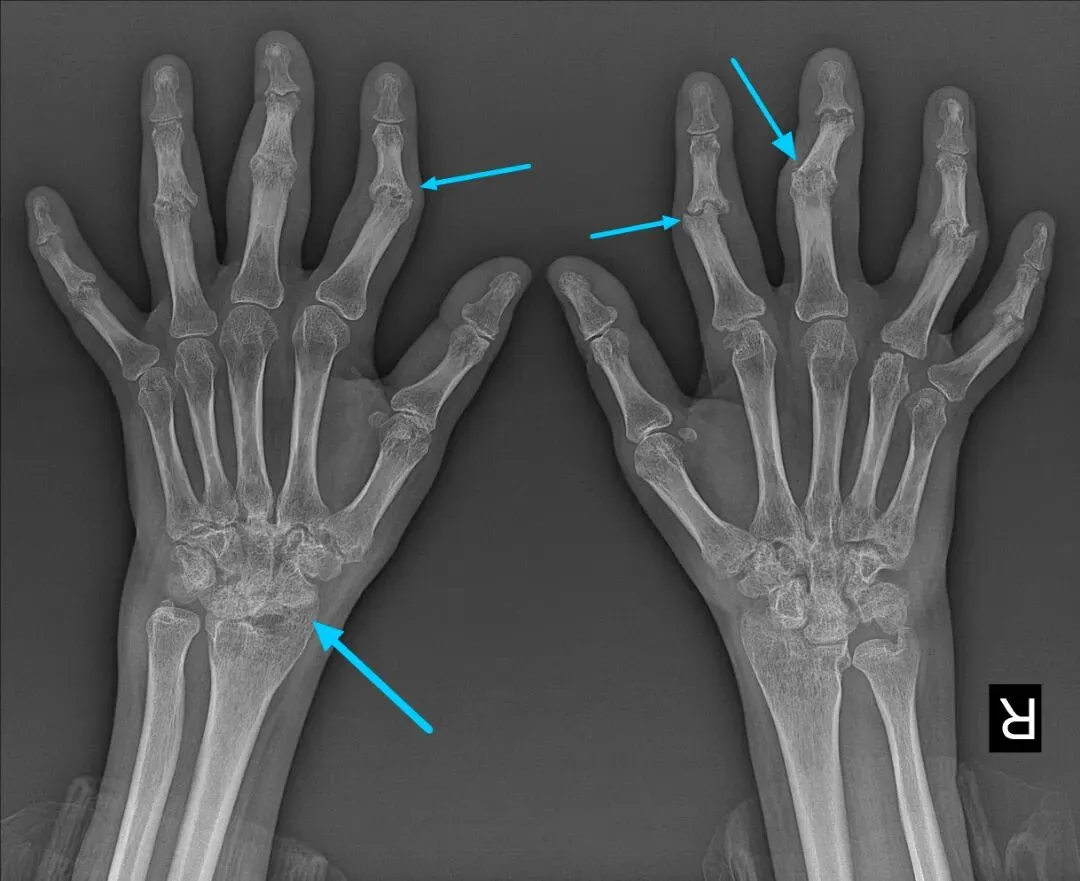

前面4项是血液检查,这一项是影像学检查,主要看关节是否出现骨质破坏、滑膜炎、关节积液等病变。早期类风湿可能X线无明显异常,可选择关节超声(更灵敏,能发现早期滑膜病变);病程较长者,X线可明确关节损伤程度,为治疗方案制定提供依据。